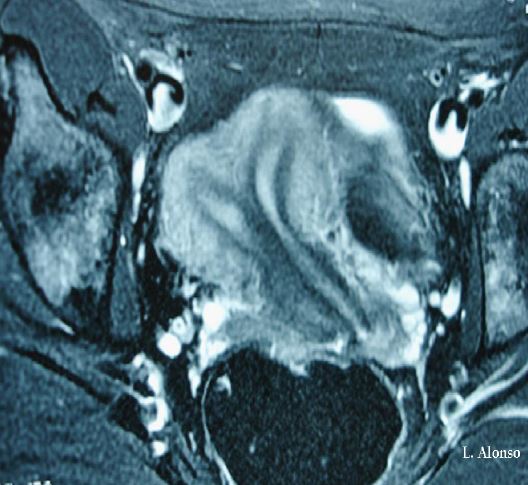

There are several imaging techniques used for the diagnosis of uterine and cervical anomalies, with a different degree of diagnostic accuracy. 2D ultrasound and hysterosalpingography have lower diagnostic accuracy than MRI, which has an accuracy for the diagnosis of Mullerian anomalies between 96-100%. In addition, MRI allows the study of the urinary system, which in some occasions have also associated malformations. 3D ultrasound has similar diagnostic accuracy than MRI.